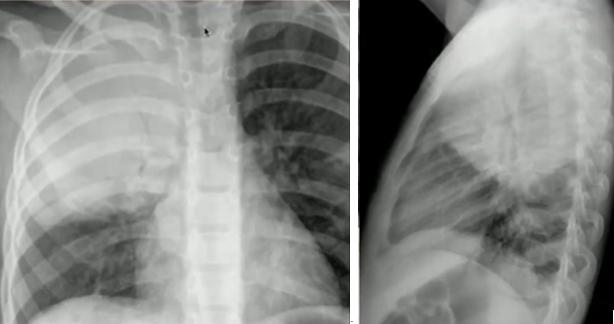

图16.正位片(左):肺不张(右上肺野肺裂上移);侧位片(右):过度充气(横隔变平)③支原体肺炎:可兼有细菌性及病毒性肺炎的表现,弥漫片状阴影或间质线性阴影,最常见表现为双下肺阴影伴积液,常伴有肺门淋巴结肿大。

图17.支原体肺炎胸片3